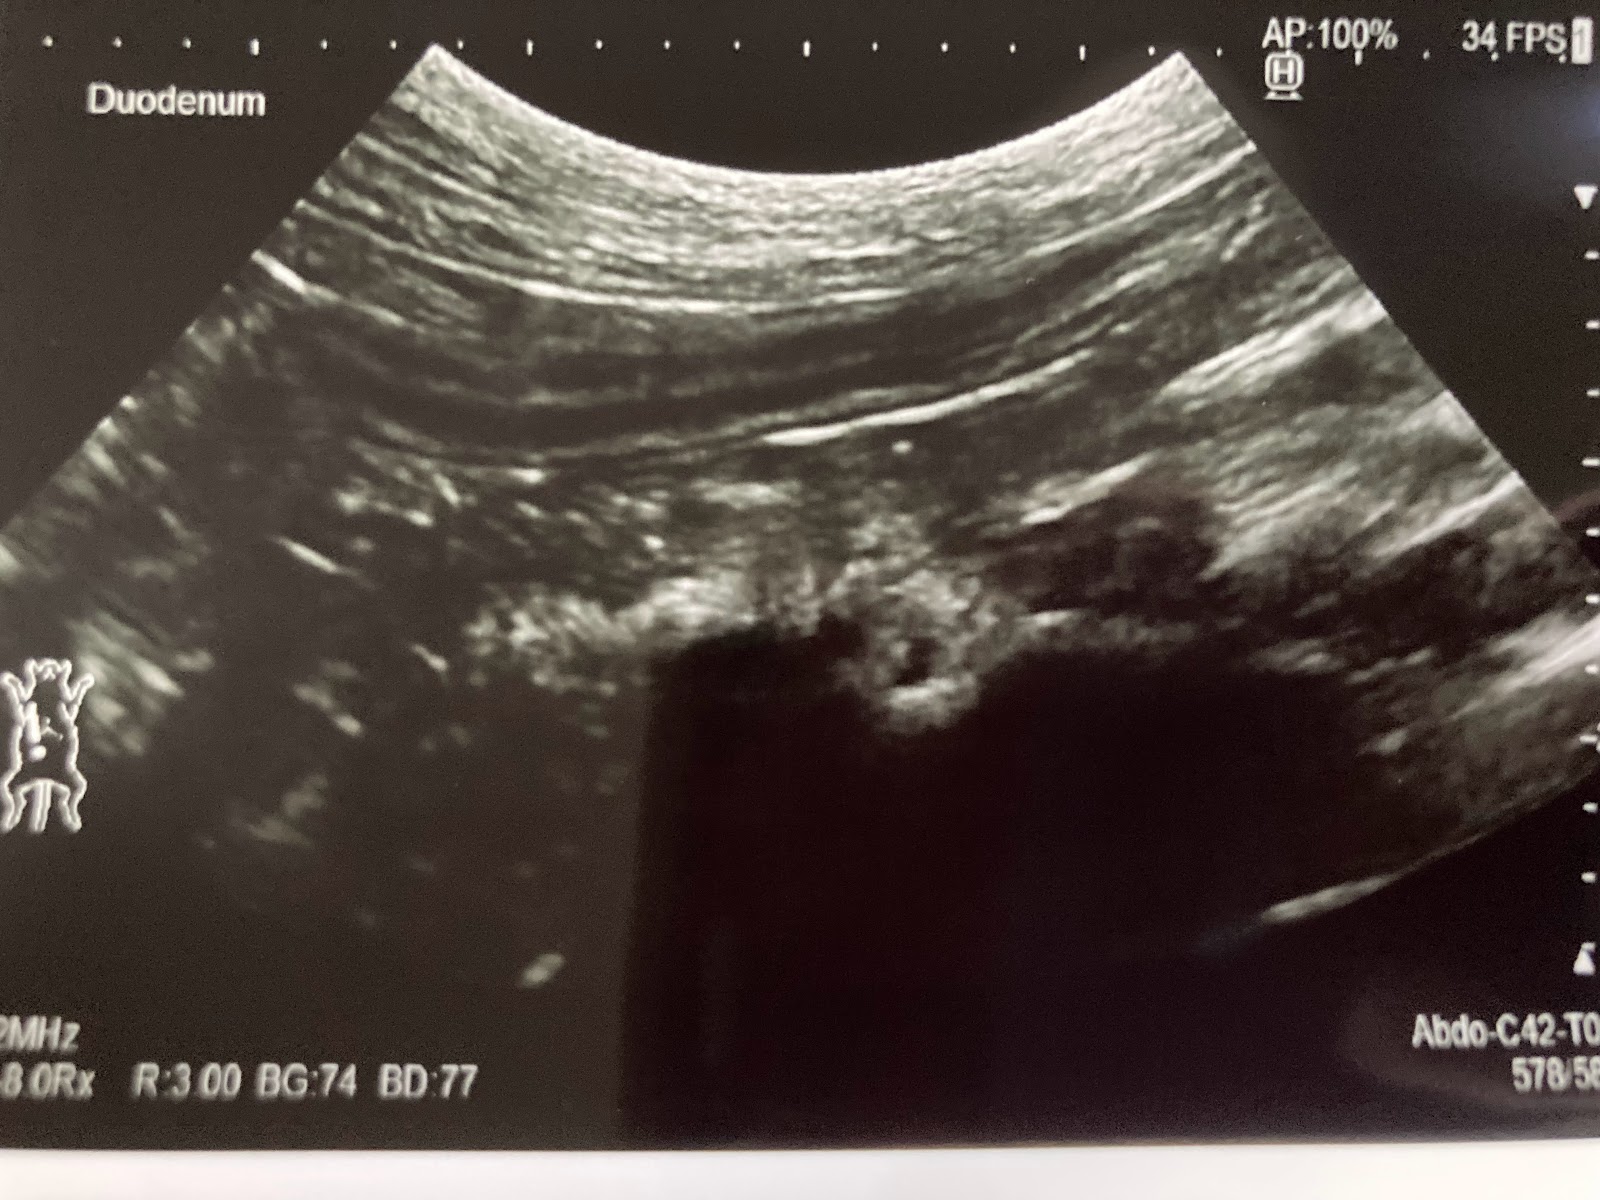

幸い今日のエコーは良かったそうで安心しています。

腸がうねうねしないでまっすぐだといいんだそうです。

ただ、胆嚢に、石までは行かないものの泥が溜まっていて、これが道を塞ぐと胆嚢炎になって手術が必要と言われています。